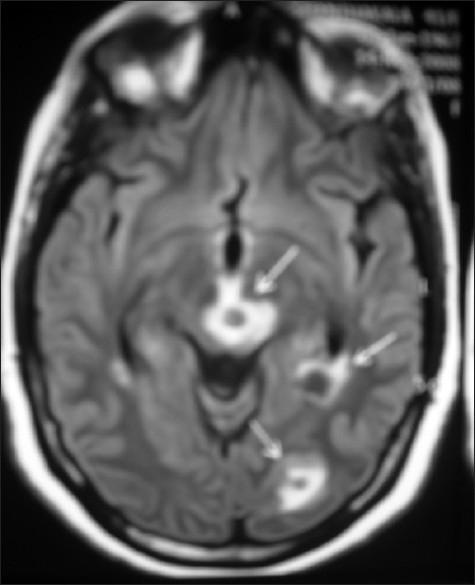

一名绝经前女性患有多器官转移的子宫内膜样腺癌。

Endometrioid endometrial adenocarcinoma in a premenopausal woman with multiple organ metastases.

Endometrial adenocarcinoma is the third common malignancy of the female genital tract occurring most often in the postmenopausal age group. High tumor grade, advanced surgical stage, and lymphovascular space invasion are implicated as poor prognostic factors for dissemination of disease. We present an unusual case of endometrial adenocarcinoma in a premenopausal woman with simultaneous metastases in brain, liver, skin and skeletal system, within one month of completion of treatment. The role of adjuvant/concurrent chemotherapy in addition to radiotherapy in high risk cases is discussed along with the review of literature.

子宫内膜腺癌是女性生殖道第三常见的恶性肿瘤,最常发生于绝经后年龄组。高肿瘤分级、手术分期晚以及淋巴管间隙浸润被认为是疾病播散的不良预后因素。我们报告了一例绝经前女性子宫内膜腺癌的罕见病例,在完成治疗后的一个月内,脑、肝、皮肤和骨骼系统同时出现转移。本文结合文献复习,讨论了高危病例中辅助/同步化疗联合放疗的作用。